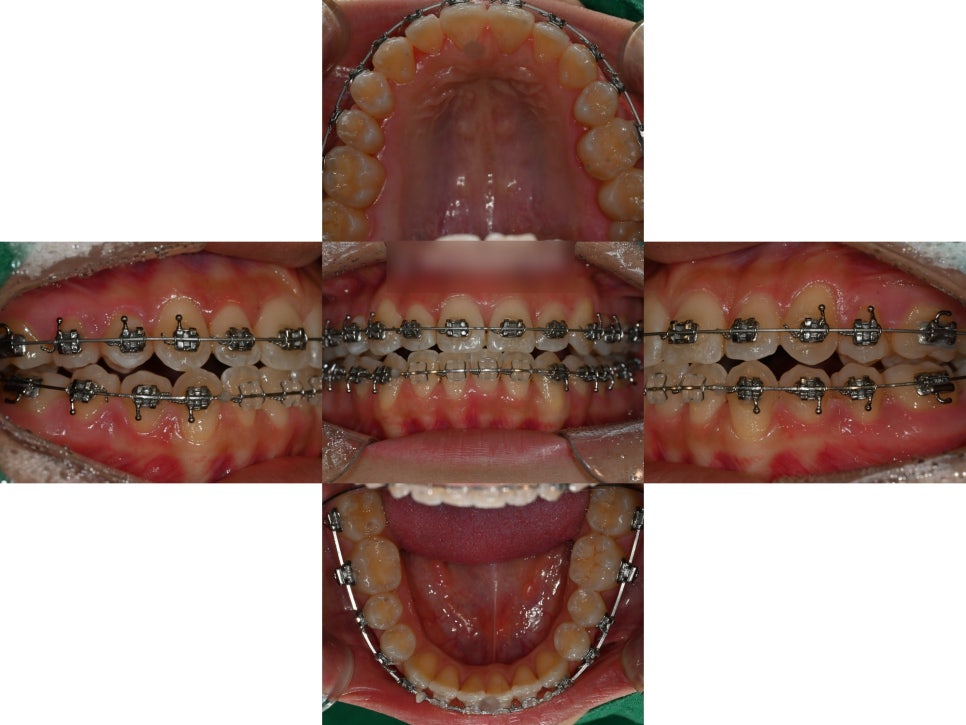

상악 확장이 잘 이루어져

윗니가 아랫니를 덮을 수 있는

상태가 되었습니다.

그러나 여전히 교합은 불안정합니다.

이제 중화동 교정치과 에서

교합을 안정화시키는 과정이

무엇보다 중요한데요.

점점 긴밀해져가는

교합의 변화를 확인할 수 있습니다.